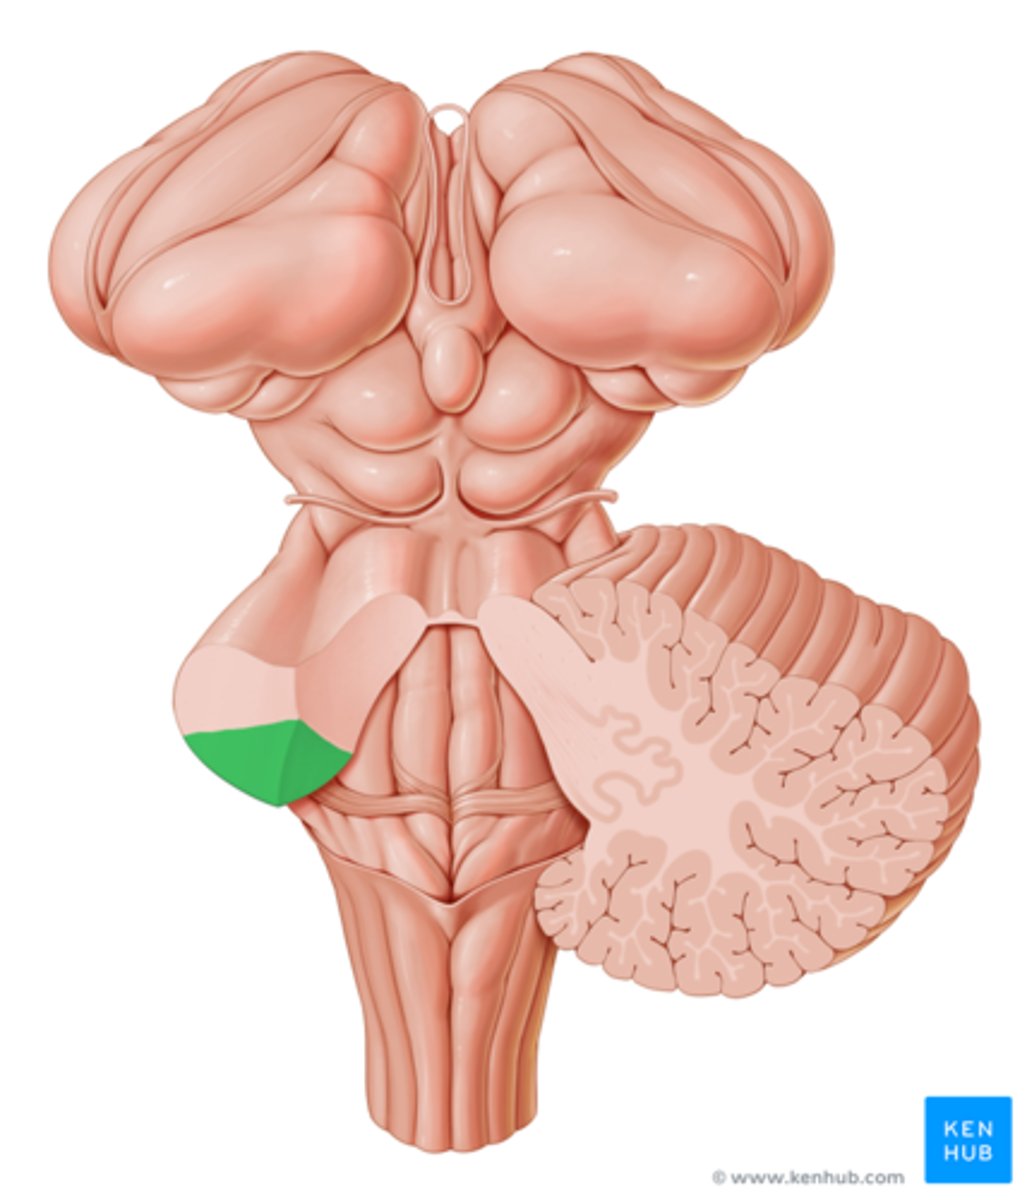

superior cerebellar peduncles

middle cerebellar peduncles

inferior cerebellar peduncles

cerebellum

right and left cerebellar hemispheres

vermis